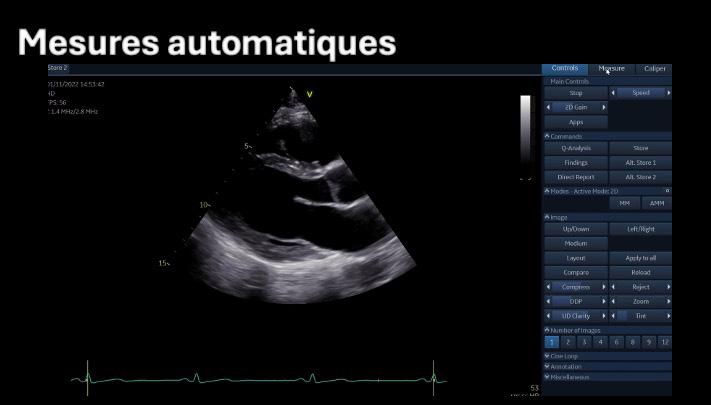

L’IA en échocardiographie 51 Quand les robots prennent la sonde